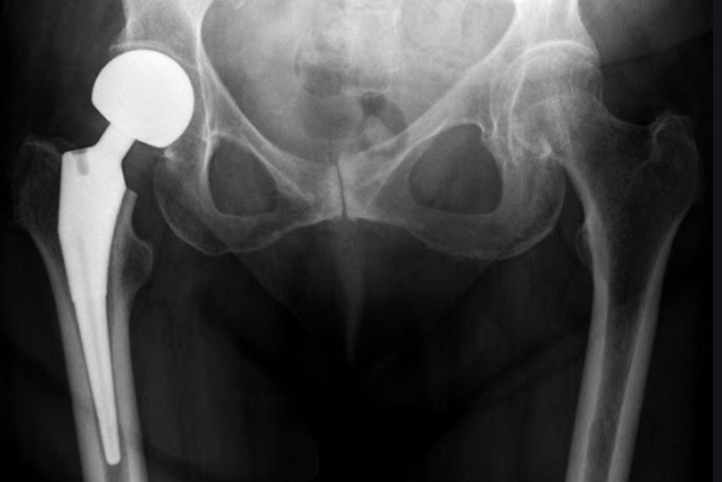

두번쨰로는 대퇴골두에만 인공뼈를 삽입하여 치환시키는 방법과 세번째로는 관절 부분 전체를 인공관절로 바꿔주는 방법이 있습니다. 이 경우에는 심하게 괴사가 된 경우에 사용하는 방법으로 합병증이 적고 기능개선이 우수하다고 알려져 있습니다.